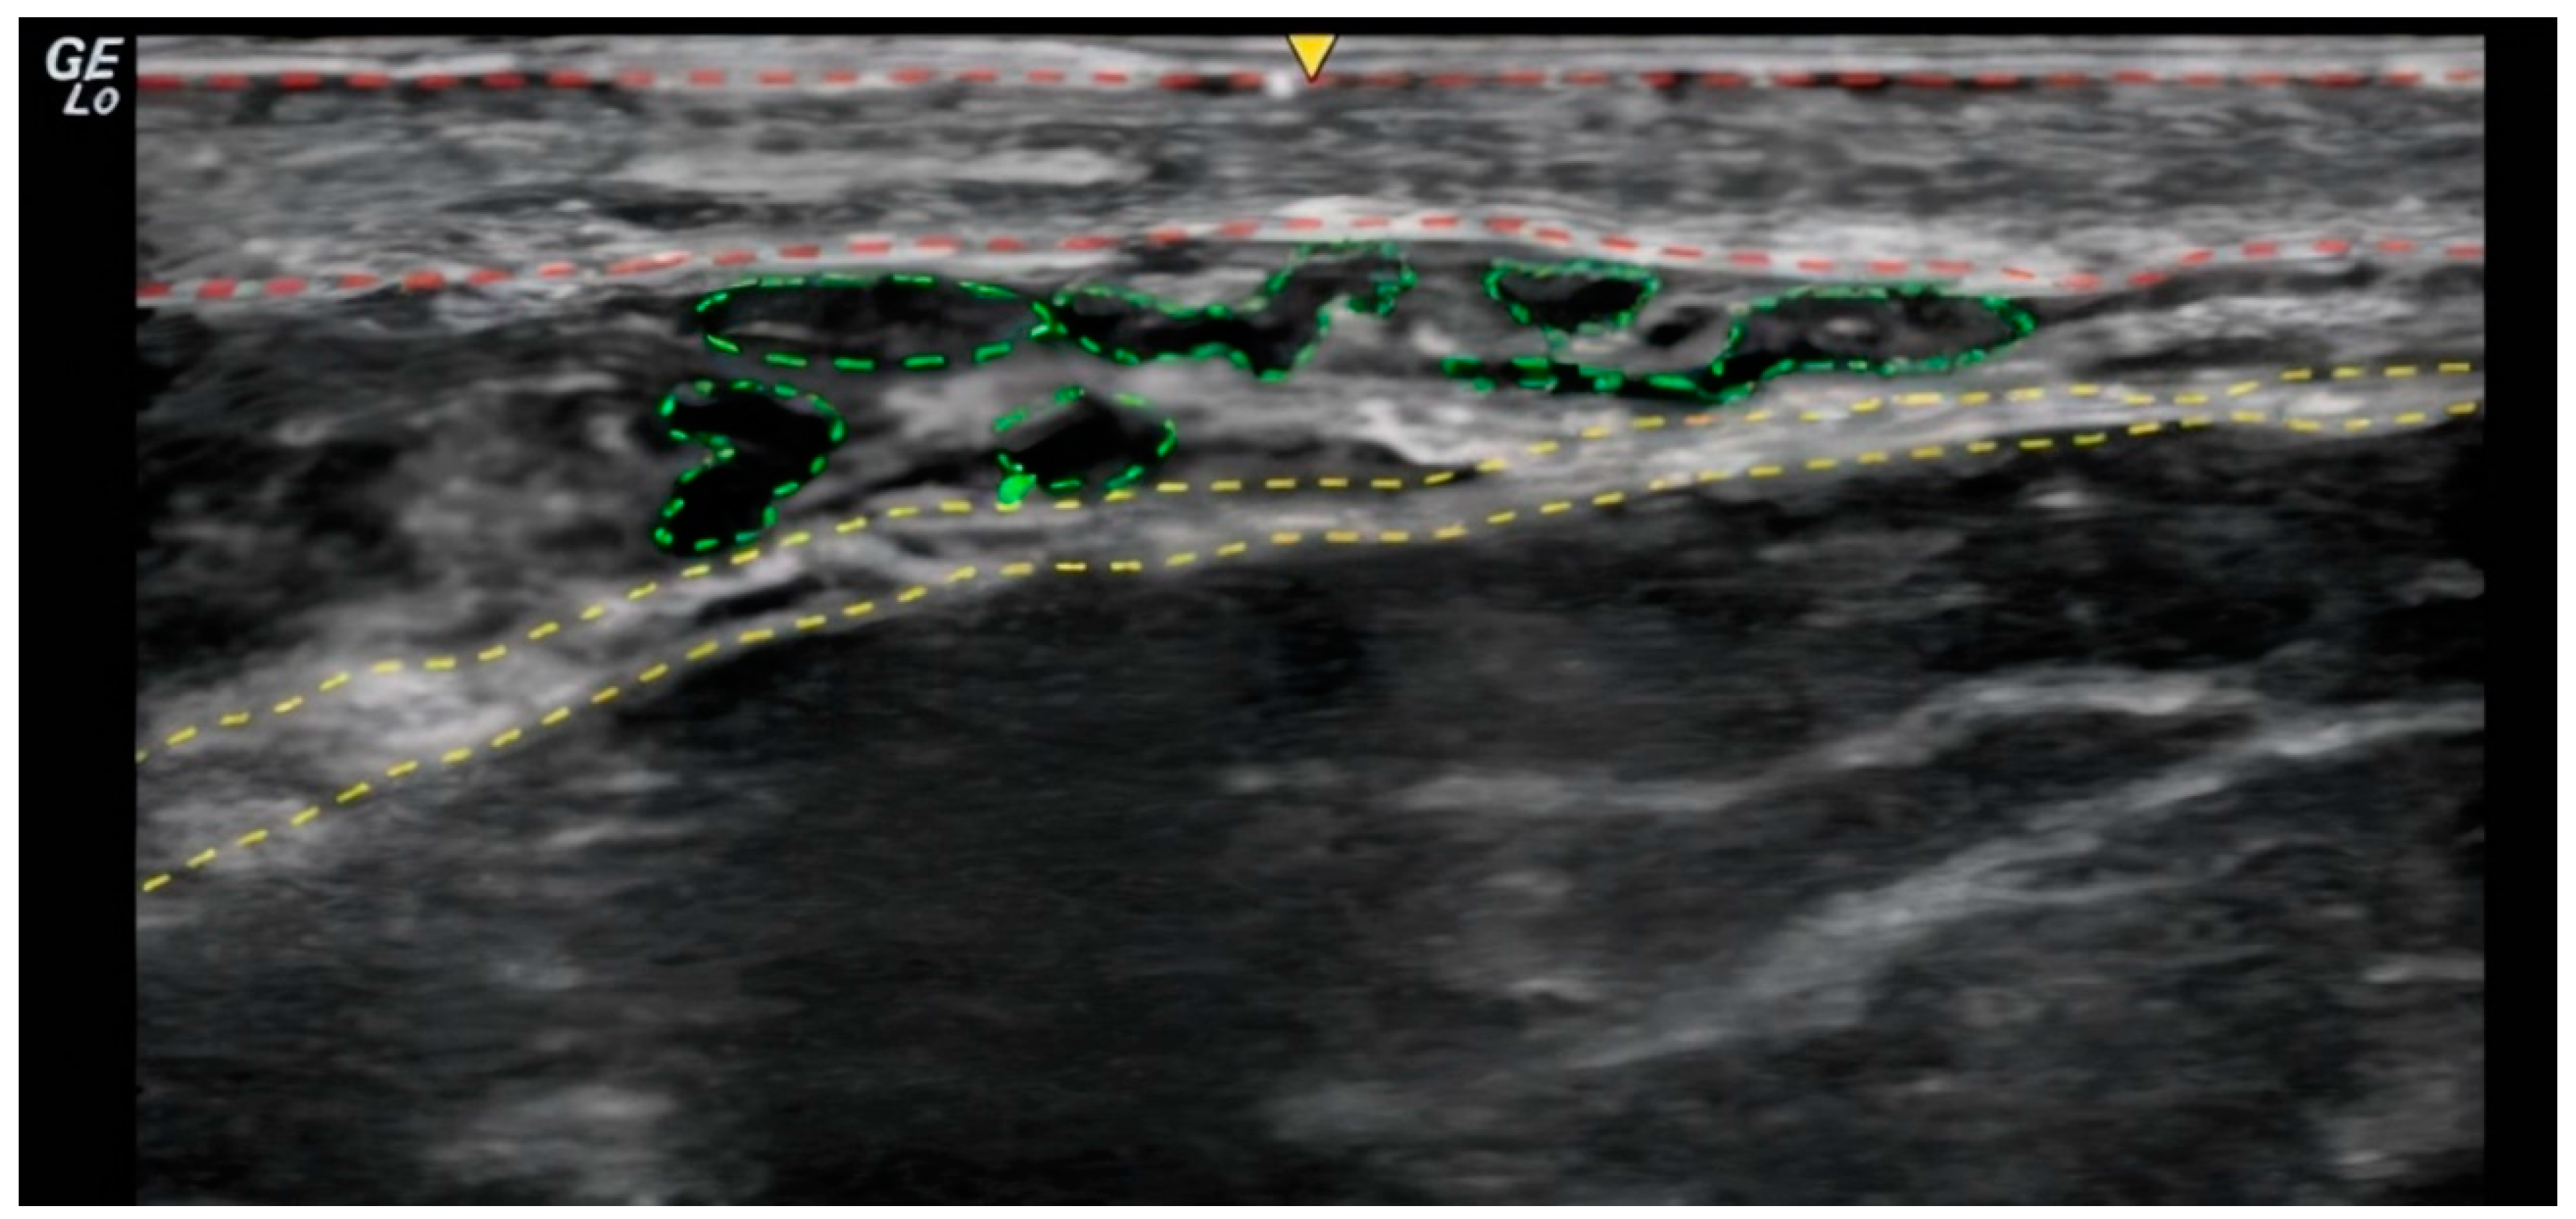

In the ultrasound examination, the correct placement of the product was confirmed in all cases and no irregularities regarding the injection site anatomy were found. (Figure 1 and Figure 2).

Patient satisfaction was assessed by patients using the 5-point S-GAIS from 1 (“exceptional improvement”) to 5 (“worsened”) (Table 1). The average rating was 3.1 at 90 days, equating to an “improved” aesthetic appearance. Interestingly, the clinical results not only remained stable but also improved over a longer follow-up period, with an average rating of 2.5 at 150 days, thereby approaching a “very improved” rating defined as “2” by S-GAIS. Put differently, 81.5% (13) of patients reported at least an “improved” (i.e., ≥ 3) aesthetic appearance at 90 days, which yet again increased to 87.5% (14) at 150 days. A similar trend can be observed in the P-GAIS, where scoring by both evaluators showed improvements at 150 days compared to 90 days after injection. Moreover, no significant correlation could be established between weight gain over the study period and changes in S- and P-GAIS. A recent meta-analysis of randomized clinical trials involving patients treated with tissue fillers for the nasolabial fold area revealed that pooled patient satisfaction was highest during the initial follow-up examination and then progressively decreased.[27] On the contrary, our finding of gradually increasing patient satisfaction highlights both the longevity and the beneficial aesthetic effects of the hyperdiluted PLLA injections over time. This may be mainly attributed to the collagen-inducing capacities of PLLA, which promotes tissue remodeling and stepwise improvements in skin quality. As PLLA microparticles are gradually resorbed by the body, they stimulate fibroblasts to produce new collagen, increasing skin thickness and firmness.[5,11,12] This process continues over several months, echoing in higher patient satisfaction at the 150-day mark.[28] To capitalize on these effects, precise product placement in the desired layer and the employed injection technique is essential: Ultrasound-guided subcutaneous placement using a retrograde fanning injection technique ensures optimal contact between the product and the dermis, thereby stimulating collagen synthesis in dermal fibroblasts (Figure 1 and Figure 2).[29]

Figure 1. Ultrasound image of the cervical region. The dermis is highlighted with red markers, indicating the uppermost layer of the skin. The product, Rennova Elleva®, is visualized in green, permeating the subcutaneous tissue layer. The yellow markers delineate the platysma muscle, demonstrating its position relative to the subcutaneous tissue and the product's distribution. This image illustrates the layering and localization of Rennova Elleva® within the anatomical structures of the neck region.